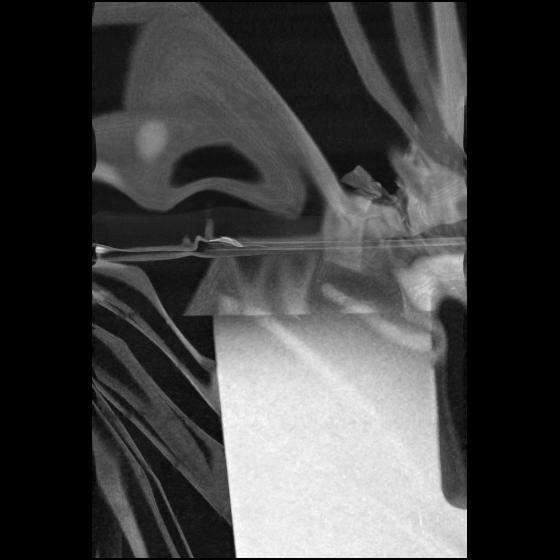

23 ANGIO,CE,Cor-MIP,5.000,ANGIO,Cor-MIP,